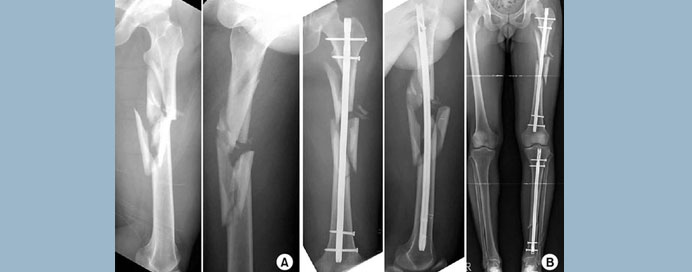

As advancements are made in the prevention of automobile fatalities, an increase in the incidence of pelvic and lower extremity injuries has occurred. These remain the leading causes of impairment and loss of years of productive life. Pelvic trauma has a high initial mortality rate when severe. However, with early resuscitation and transport, more survivors arrive in our trauma centers harboring these injuries. Owing to early stabilization and mobilization of the traumatized patient, a decrease in complications in these patients has been noted. Both the trauma surgeon and the orthopedic trauma surgeon should work as a team and remain in continuous communication during the treatment of these patients. Open fractures are among the most difficult problems to manage; early and aggressive decisions can prevent a lifetime of complications and physical impairment. As previously stated, to obtain good outcomes, open fractures must be treated initially at the accident scene followed by timely transport to the trauma center for definitive care. It must be remembered that the golden time to prevent major complications is 6 hours. Intra-articular fractures of the lower extremity involve a major weight bearing joint. Post-traumatic arthritis and impairment develop in joints where joint congruity is not achieved. To preserve normal function, there should be articular congruity, stable fixation, axial alignment with the rest of the extremity, and restoration of full range of motion. Immediate stabilization of long bone fractures has many advantages in the multiply injured patient, such as improved long-term function, prevention of deep venous thrombosis and decubitus ulcer, decreased need for analgesia, and reduction in the incidence of adult respiratory distress syndrome and fat emboli. Patients with femoral shaft fractures should undergo immediate stabilization of the fracture within 24 hours of injury. We have presented a series of orthopedic injuries that have high mortality and high morbidity which, if not treated expediently, yield a high degree of impairment.